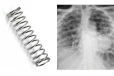

இந்த நிலையில் 2 ஆண்டுகளுக்குப் பிறகு மீண்டும் ஹினா கான் கருவுற்றார். பின்னர் பிரசவத்திற்காக மருத்துவமனையில் அனுமதித்தனர். அப்போது ஹினா கான் வயிற்றில் ஒரு தையல் ஊசி இருப்பதைக் கண்டு அதிர்ச்சியடைந்தனர். இதனை அறுவை சிகிச்சை மூலம் குழந்தை மற்றும் தையல் ஊசியை அகற்றினர்.

இந்த ஊசியால் குழந்தை பலத்த காயம் அடைந்தது. மேலும் உயிருக்கு ஆபத்தான நிலையில் வென்டிலேட்டரில் வைக்கப்பட்டுள்ளது. இந்த சம்பவத்தில் ஆத்திரமடைந்த குடும்ப உறுப்பினர்கள் காவல் நிலையத்தில் புகார் அளித்தனர். புகாரின் பேரில் வழக்குப் பதிவு செய்த காவல் துறையினர் விசாரணை மேற்கொண்டனர்.

முதற்கட்ட விசாரணையில் முதல் பிரசவத்தின் போது மருத்துவர்கள் அலட்சியத்தால் தவறுதலாகத் தையல் ஊசி வைக்கப்பட்டது தெரியவந்தது. இதன் காரணமாக தான் ஹினா கான் வயிற்றுவலியால் துடித்து வந்தது தெரியவந்தது. மேலும் சம்பந்தப்பட்ட மருத்துவர்கள் மீது நடவடிக்கை எடுக்க வேண்டும் என்று குடும்ப உறுப்பினர்கள் வலியுறுத்தியுள்ளனர்.